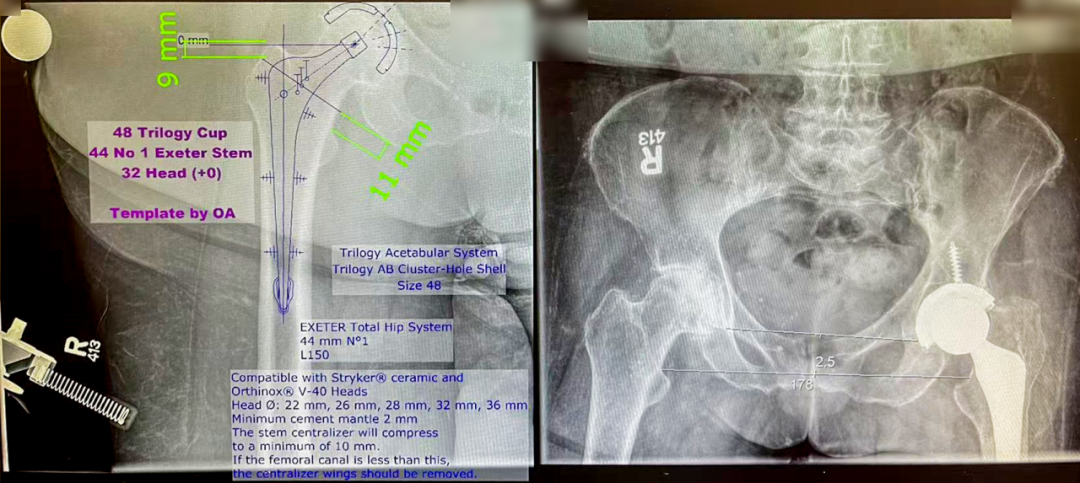

然后是医院的重点——手术,作为多伦多大学附属医院的骨科关节中心(从总院独立出来在市中心建立的单独手术室的骨科中心),每年的关节置换手术量有3500多台,而且以复杂关节和关节置换后翻修手术为主,吸引了全加拿大的各类患者前来就诊。

HollandCentre作为骨关节置换中心,同国内相关单位,有其明显特色:

1. 目前大约70%的关节置换患者是DaySurgery,即做完手术当晚直接回家!后续治疗直接通过家庭医生与手术教授联系,门诊定期随访(第一次术后3周,第二次术后3-6月),从医疗体系来看,确实极大减少了患者的负担,降低了医疗支出(每住一天,需要支付费用大概1400加元,折合人民币7100元左右),节省了医疗资源,目前他们医生和麻醉医生、镇痛医疗组正在努力将日间手术当天出院患者比例提高到80%。

2. 高风险手术患者占比较多,因为人种的差异,这里的患者,高BMI的比例相当高,部分患者甚至接近50!!(18.5 kg/m² ≤ BMI < 24 kg/m² 正常范围值,≥28 kg/m²属于肥胖)对骨关节科医生而言是前所未有的挑战,但是SunneyBrook的骨科专家经过详细的术前讨论、术前规划后,小心而细致地进行了关节置换或者翻修手术,术后创面直接负压吸引(类似于国内的VSD)2周,疗效较好。

另外,对于术后感染需翻修和超高龄(大于90岁)的关节置换,他们也积累了丰富的经验,会在准备完善后进行手术治疗。

3. 植入材料的选择上,既往存在的观念是,国外的一定选用最先进最好的材料,其实并不是,很欣赏Dr.Nousiainen的话:The skilled is the best。他们选择的大部分都是多年使用成熟的植入物,对其特性和适应症非常熟悉,出现任何情况知道如何处理,并不会贸然使用所谓最新最贵的材料(甚至有一款目前国际流行假体就是我所在医院的教授发明并使用的)。